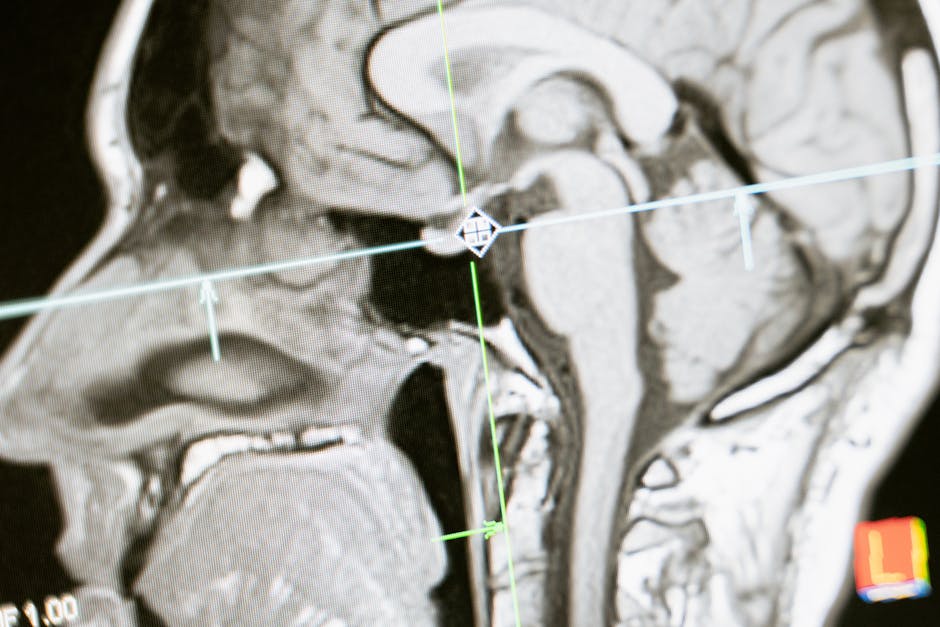

The concept of dad brain is not just a figure of speech, but a real neurological phenomenon that has been observed in studies. Research has shown that the brains of new fathers exhibit changes in the structure and function of certain regions, including the amygdala, the hypothalamus, and the anterior cingulate cortex. These changes are thought to be driven by the release of hormones such as oxytocin, vasopressin, and testosterone, which play a crucial role in bonding, attachment, and parental behavior. As a result, new fathers often experience a range of emotional and behavioral changes, including increased emotional sensitivity, reduced aggression, and a stronger desire to nurture and care for their children.